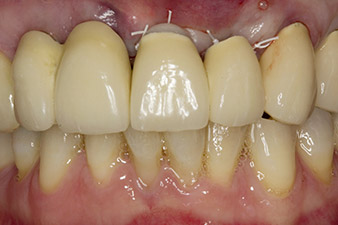

Un patient de 67 ans s'est présenté en consultation avec des couronnes jumelées à remplacer dans le maxillaire.

Lorsque le patient s'est présenté pour la première fois, les dents 21, 22 et 23 avaient été restaurées il y a 19 ans à présent, par des couronnes jumelées collées sur les implants en position 12/11 à l'aide d'une attache

(cf. Fig. 2).

La radio a révélé une perte osseuse horizontale autour des dents 21 et 22 (Fig. 1). Lorsque la structure de couronne a été retirée, ces dents ont involontairement été extraites en même temps.

La dent 23 présentait une fracture coronaire horizontale et un matériau de reconstitution du moignon et de scellement des tenons a été utilisé à titre de restauration temporaire. L'objectif était de poser un bridge en oxyde de zirconium sur les implants existants aux positions 12 et 11 et de poser deux nouveaux implants aux positions 22 et 23.